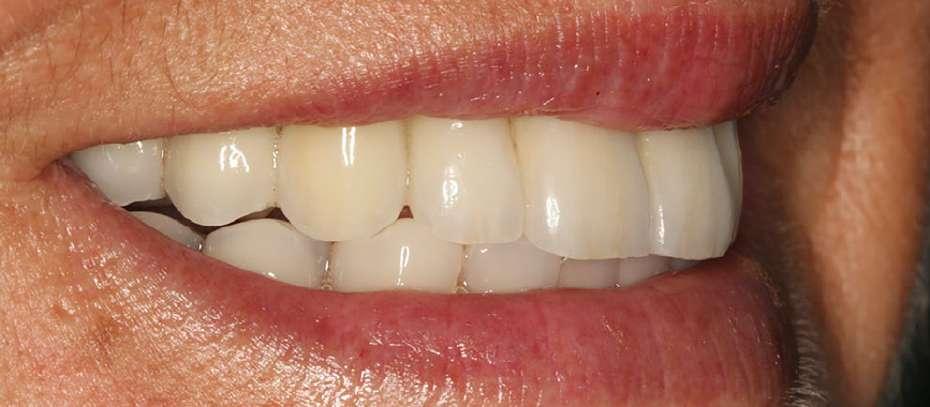

Tres meses después de la cirugía inicial podemos realizar una nueva prótesis que se adapte al nuevo patrón oclusal, mejorándose la estética. Se aprove-

cha en este punto para retirar las mini-placas mandibulares y en las imágenes de la cirugía podemos observar cómo se ha producido una regeneración completa del lecho óseo (figuras 13-16). La prótesis definitiva recupera todos los parámetros deseados de estética, función y oclusión, además de un tercio facial inferior compensado (figuras 17-19). Estos cambios son mucho más evidentes cuando comparamos las imágenes inicial y final del caso. Podemos observar un tercio facial mucho más armónico además de una compensación de la anchura facial acortándose el rostro y ampliándose la base nasal (figura 20).

Figuras 17-18. Imagen intraoral de la paciente con la prótesis finalizada y la radiografía. Figura 19. El cambio facial es evidente en la imagen frontal, compensándose el tercio inferior.

La paciente continúa en seguimiento durante los años siguientes, manteniéndose estable el tratamiento y la estética facial lograda. A los 10 años podemos ver imágenes donde se mantiene la compensación del tercio facial y la prótesis sobre implantes con una buena relación diente-labio. A los 14 años, la expresión facial sigue compensada y la estética de la paciente satisfactoria además de no encontrar pérdidas óseas significativas en los implantes (figuras 21-22). Los implantes no presentan pérdidas óseas significativas en todo el seguimiento. La radiografía final muestra una estabilidad completa de ambas rehabilitaciones. Hoy en día, probablemente los implantes hubieran presentado una menor longitud, ya que los protocolos terapéuticos cambian, pero hace 14 años, se realizaron con las ideas dominantes en el momento de inserción de implantes de mayor longitud posible para soportar mejor la biomecánica de la masticación. Tras 22 años de seguimiento, hemos realizado algunas modificaciones en la estructura de la prótesis inferior, pero seguimos conservando la estabilidad del tratamiento (figura 23-26).

Figuras 23-25. Imágenes de la paciente en el seguimiento a los 23 años. Vemos la expresión facial, la estética de la sonrisa y el soporte labial que permanece inalterable con el paso del tiempo.